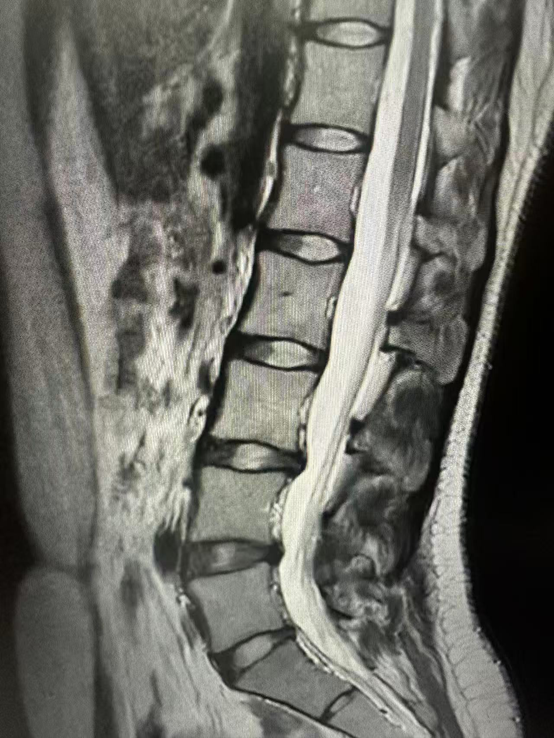

3.磁共振成像(MRI)检查:

MRI对软组织的分辨能力很强,可以清晰地显示椎间盘、脊髓、神经根、韧带等结构。通过MRI,医生能够准确判断椎间盘突出的程度、是否压迫到脊髓和神经根,以及神经是否有水肿、变性等情况,是诊断腰椎间盘突出症、腰椎管狭窄症等疾病的重要检查方法。